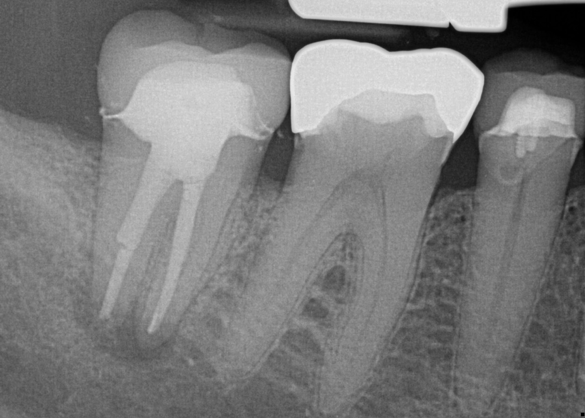

Treatment of combined endodontic and periodontal lesions does not differ from the treatment of either an endodontic lesion or a periodontal lesion. The part of the lesion sustained by the root-canal infection can usually be expected to resolve after proper endodontic treatment. Timing of the completion of the root-canal therapy, medicaments used, and assessment of restorability are considerations for the long-term success and survival of the tooth.7 Figures 7, 8, and 9 represent the timing of completion and restorative decision-making to complete all therapies.

In Figure 7, the periapical radiograph identifies the presence of the combined endodontic-periodontal lesion developing due to a carious lesion beneath an existing vintage gold crown with ill-fitting margins. Intraoral examination revealed a fistula developing and moderate pain on percussion and mastication. After occlusal access and clear visualization of the canals, the canals were shaped using the rotary files, with precautions taken not to perforate or enlarge the apical foramen. Maintaining the endodontic therapy within the canals prevents the infection from being introduced into the surrounding periodontium. In this case, calcium hydroxide medicament was placed into the canals and evaluated 30 days postoperatively.8

Fig 7. Primary endodontic and secondary periodontal lesion, mandibular second molar.

Figure 7